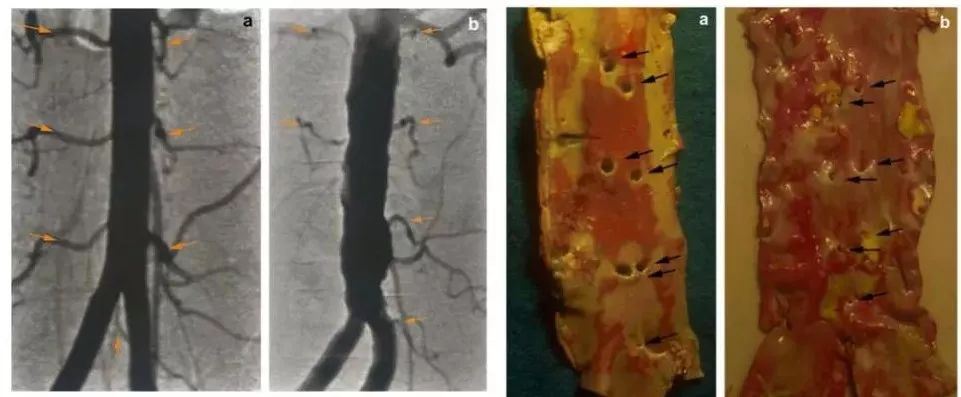

上图中,靠左的两幅图是椎动脉血流的造影;它们对应右边主动脉硬化程度的照片[12]。

当主动脉硬化很轻,主动脉向椎动脉分支的开口(小眼)是通畅的;当主动脉硬化严重时,这些开口被堵住了。

接下来这张图,是四位病人(已过世)的主动脉纵切照片[10]。

从左往右,他们的动脉硬化情况越来越严重。

最左边是动脉硬化最轻的主动脉,我们还能看到主动脉壁上一对一对的小眼,这些小眼就是主动脉在对应于每节腰椎的位置上,分支椎动脉的开口。

血液从主动脉流下来,要流入这些小眼进入椎动脉,给椎间盘供血。当主动脉硬化越来越严重……我们看最右边的图,那些开口小眼被堵死了。

主动脉到椎动脉的通道堵死了,我们的椎间盘就失去了血液供应,椎间盘的结缔组织就会萎缩坏死,里面的包浆就会减少……